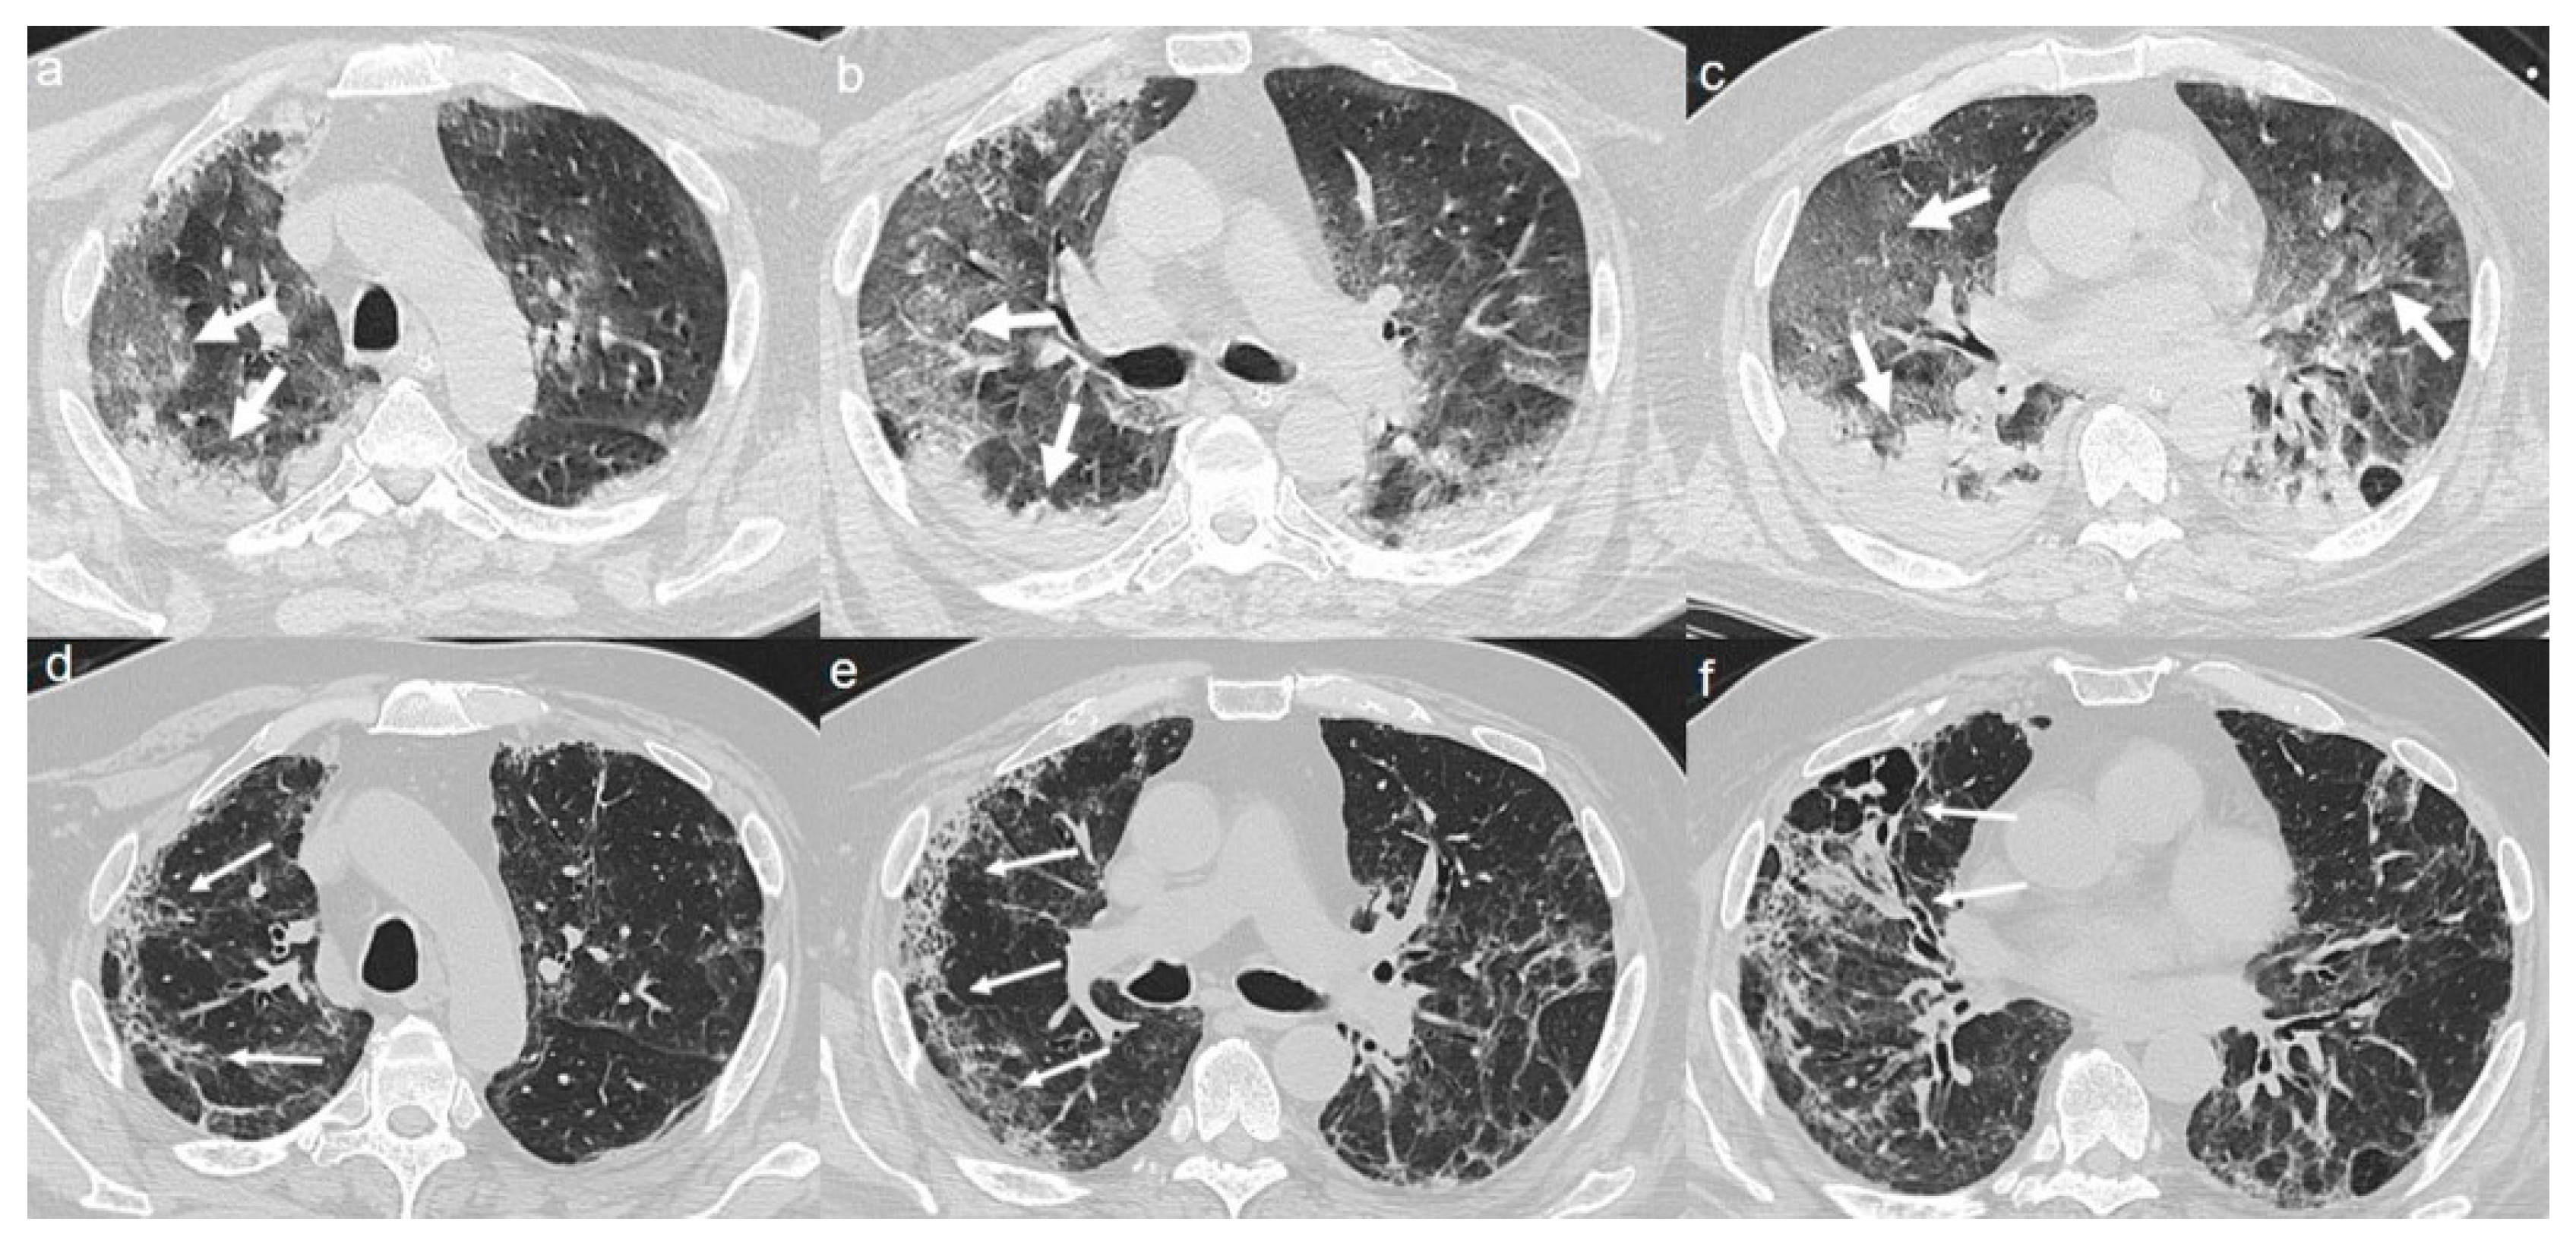

On admission, chest CT showed a diffuse “crazy paving pattern” peripherally located in the upper and lower lobes (Figure 3a–c).

Figure 3.

(a–c) CT shows a “crazy paving pattern” peripherally located in upper and lower lobes (arrows). (d–f) CT after 4 months from the onset of symptoms shows bilateral persistence of mixed pattern of GGOs (thin arrows in d) and fibrous streaks (thin arrows in e,f).

A CT at 4 months from the onset of symptoms revealed the bilateral persistence of a mixed pattern characterized by GGOs and fibrous streaks (Figure 3d–f).